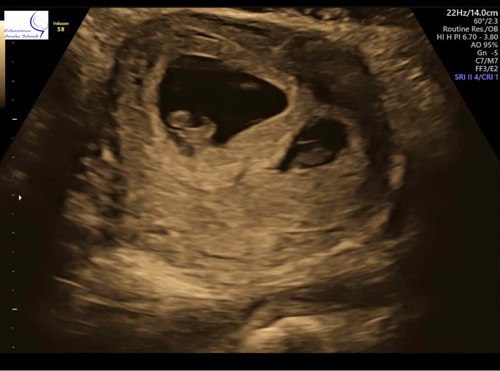

Echo met 7 weken en 2 dagen. Iemand enig idee wat die witte waas is? Dooierzak? Of schemering? Zag het pas toen ik thuis was.